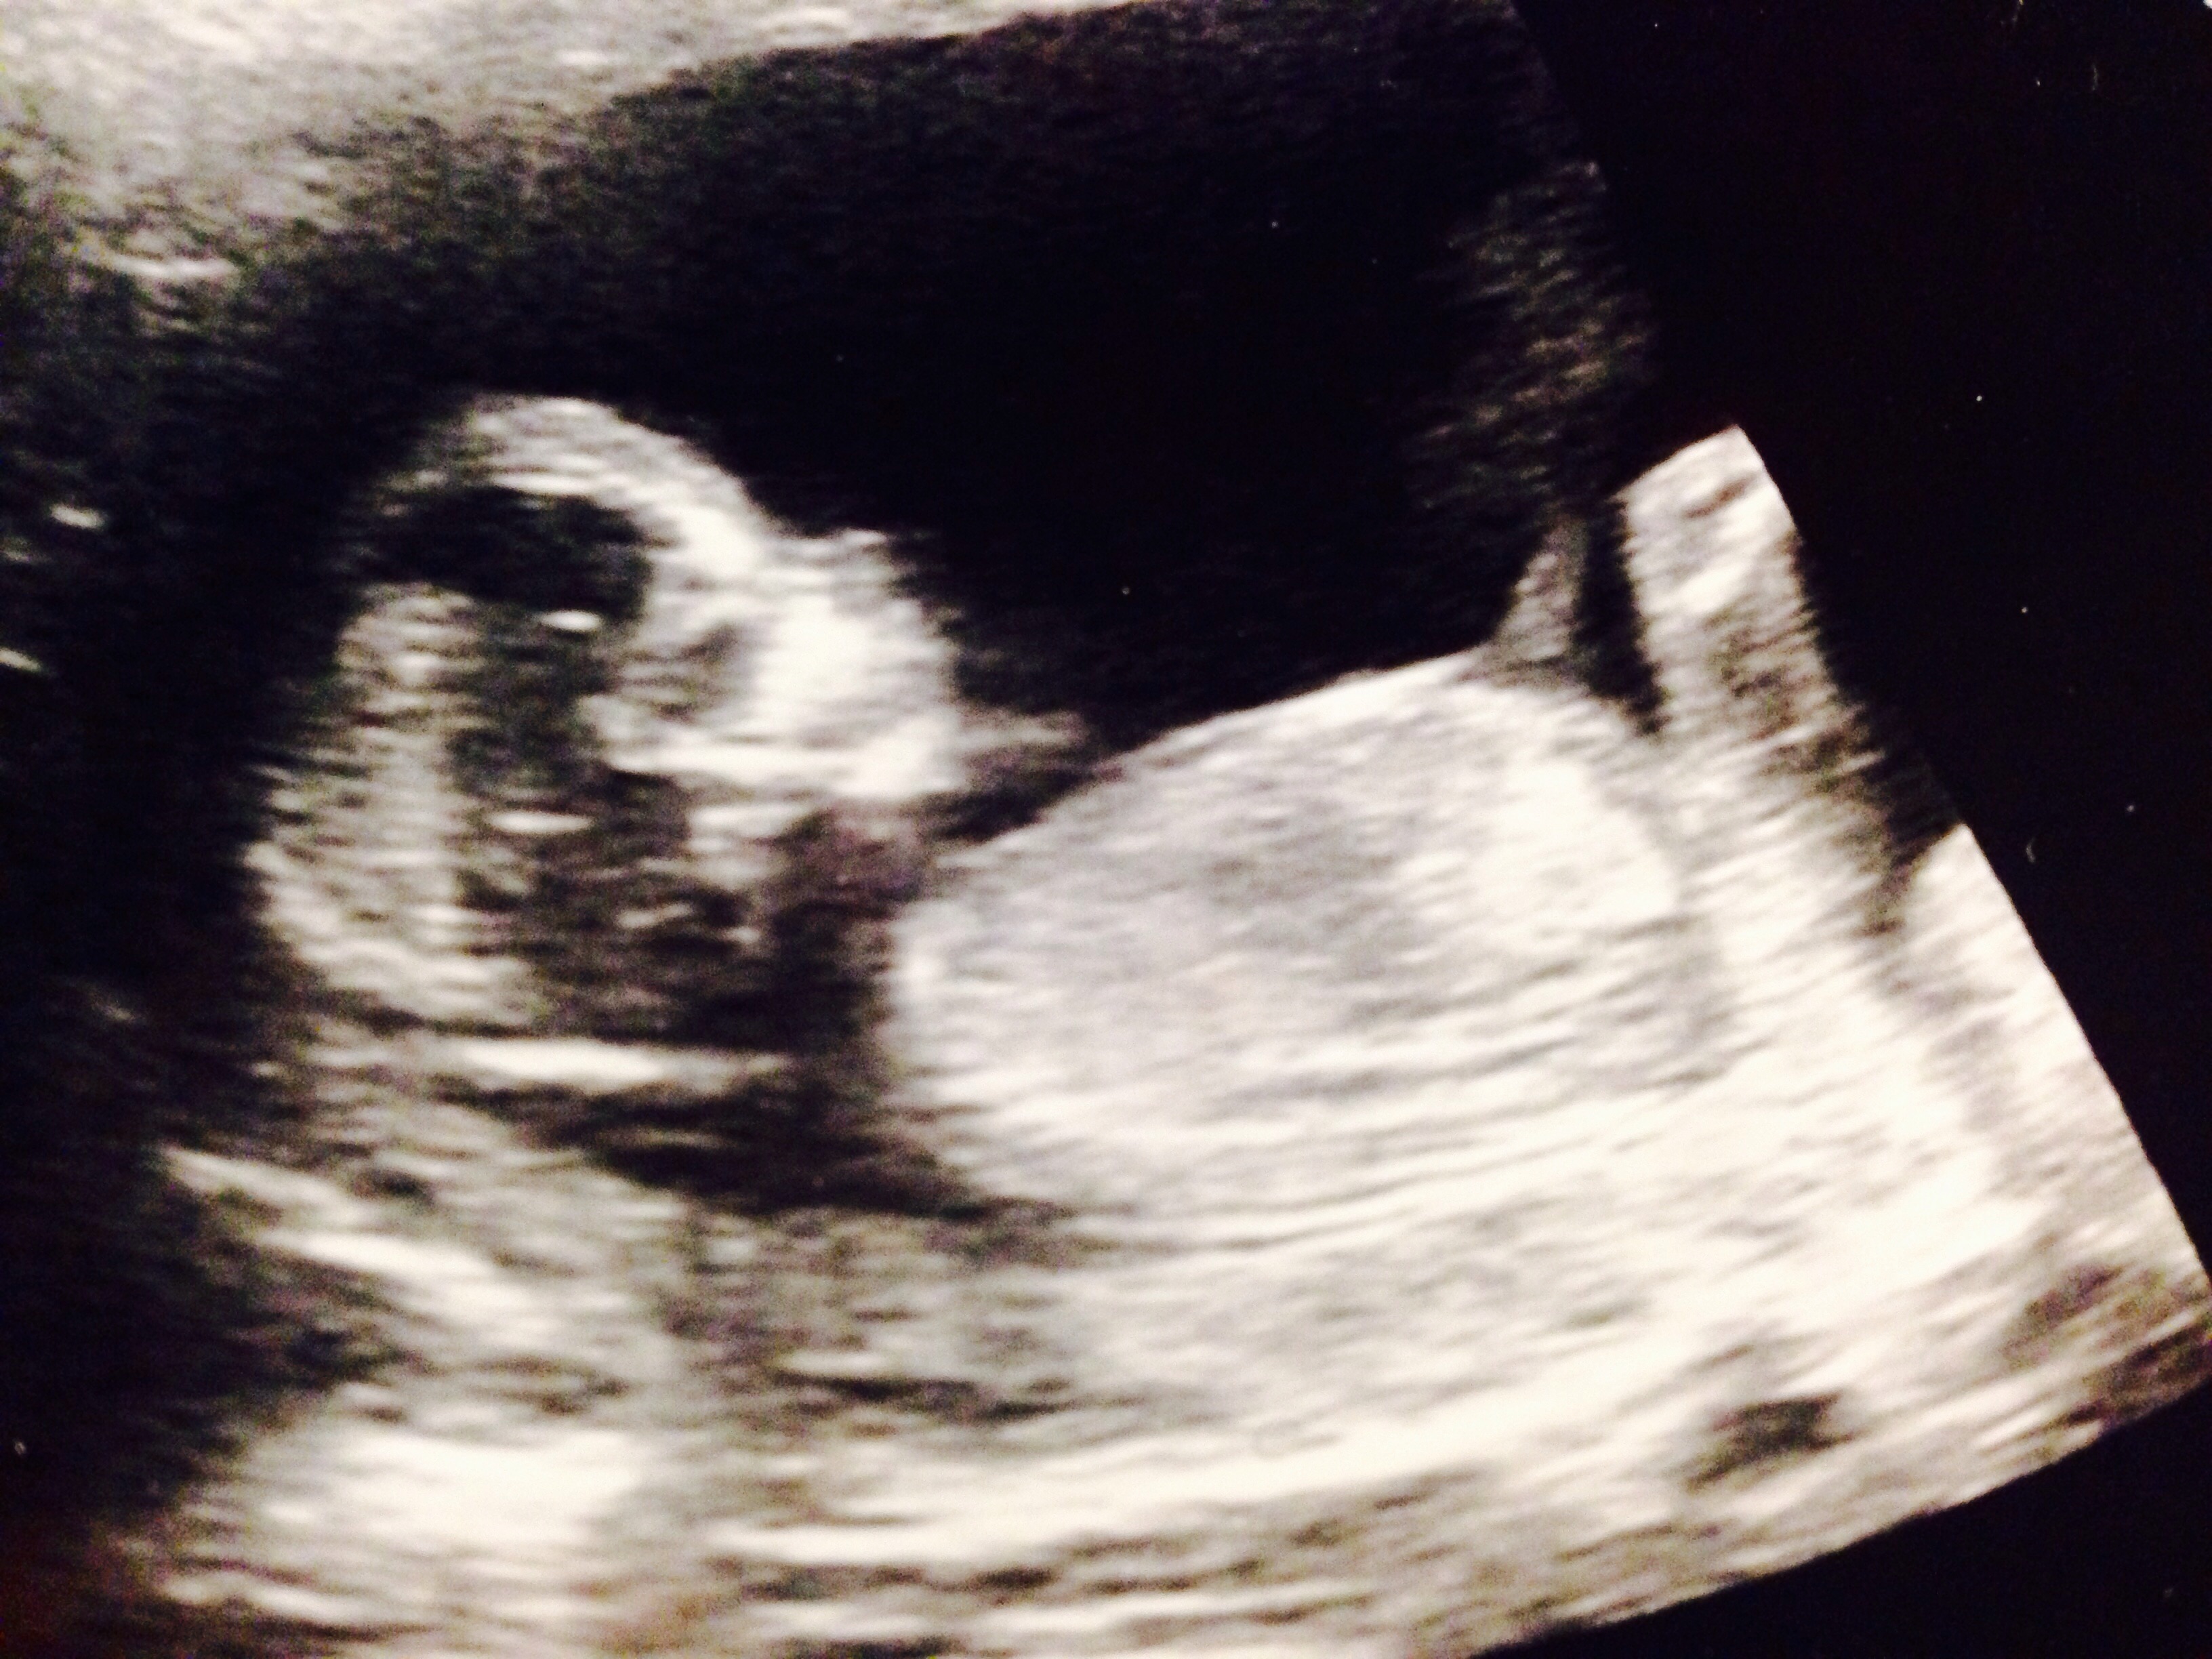

Can anytjing be seen clear enough to take a guess?

If what I'm seeing is the nub, I agree, girl!

There is a very fuzzy nub but I lean girl

If it's the nub what I see then I think girl. No better pic?